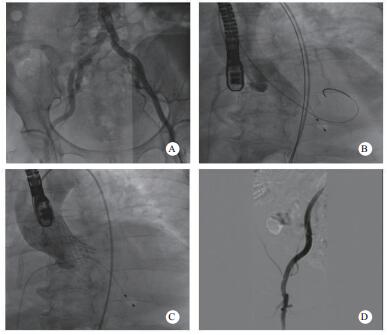

(2)血管造影明确双侧髂股动脉入路情况,选择条件更好的一侧进行手术本病例通过超声引导下穿刺左侧股动脉,但J型导丝难以通过股左侧髂总动脉,提示血管可能存在严重狭窄。随后的造影可见双侧髂总动脉均有不同程度的病变,右侧相对较好(图 2A),故选择右侧作为主入路进行手术。超声引导下穿刺右侧股动脉,置入19 F大鞘内芯,通过有阻力,考虑血管条件差,放弃置入19 F鞘。因瓣膜输送系统的外径与16 F大鞘外径相当,采用无鞘植入的方案,改成16 F cook鞘置入,顺利通过。

|

| A:外周血管造影;B: 20×40 mm Z-Med球囊行Balloon Sizing;C:植入26 mm Venus-A瓣膜后复查造影;D:复查外周血管入路造影 图 2 患者造影 |

明确冠状动脉情况:该患者有右冠PCI手术史,合并高血压和糖尿病,可能存在需要处理的冠脉病变,所以在置入大鞘后对该患者进行冠脉造影检查,结果提示右冠支架通畅,前降支及回旋支轻-中度狭窄,无需干预处理。

(2)选择合适大小的球囊进行Balloon Sizing测量:在明确上述情况后,还需要选择合适的球囊进行Balloon Sizing测量,同时观察冠脉血流情况进一步评估瓣膜释放后可能出现的冠脉堵塞情况。因术中基于超声测得的瓣环内径为2.11 cm,故选择20 mm×40 mm Z-Med球囊进行测量,在球囊膨胀到最大程度时,可以看到球囊两侧仍存在少量反流,且无明显腰征,左冠及右冠血流通畅(图 2B)。

选择合适大小的瓣膜植入并评估;根据超声和球囊测量的结果,针对该患者,最终选择26 mm Venus-A瓣膜进行手术,植入位置理想,几乎无瓣周漏和跨瓣压差,冠脉血流未受影响(图 2C),复查外周血管造影提示未见明显狭窄及出血(图 2D)。